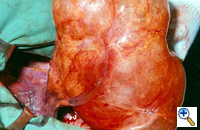

Group I: Single large bulla with normal underlying lung (Figure 1)

| Figure 1: Operative view at thoracotomy of a single bulla with normal underlying lung. | Figure 2: Operative view at thoracotomy of multiple bullae with underlying lung with diffuse emphysema. |